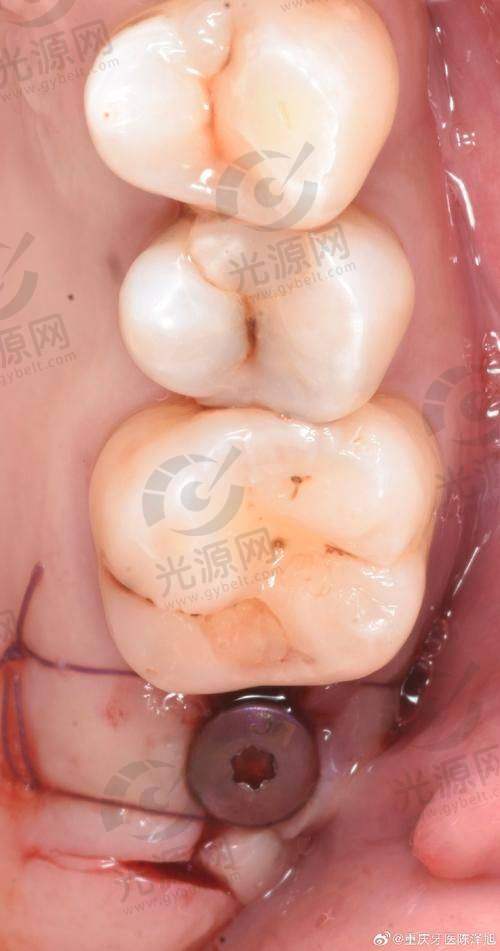

二、诺贝尔种植牙的技术优势与医生水平

诺贝尔种植牙在技术上引入了领跑的微创手术理念,较大限度减少患者的疼痛和术后修复时间。医院的种植牙医生均接受过专精的国内外培训,并持有相关资质证书。例如,诺贝尔的Active系列种植体因其独特的螺纹设计和亲水性表面,能与骨组织快速结合,提供出色的初始稳定性,极大提高了种植成功几率。此外,医院根据每位患者的具体情况,制定个性化的种植方案,确保治疗的针对性和有效性。特别多患者在接受种植手术后的反馈中表示,术后的修复非常快,成效非常自然,这得益于医院采用的高端技术和设备。通过不断的技术创新和学术交流,诺贝尔口腔医院的种植牙服务赢得了患者的高度认可,许多患者表示愿意推荐给身边的朋友和 family。